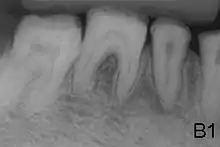

| Amelogenesis imperfecta, hypoplastic type. Note the association of pitted enamel and open bite. | |